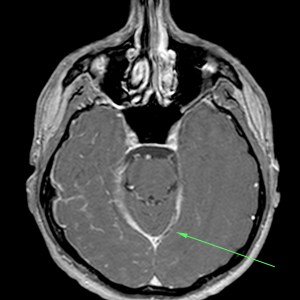

Se procede a la intervención de la paciente con realización de Arteriografía.

- Signos directos: Signo del Delta Vacío (signo directo más frecuente – 30%). Es un trombo triangular en el interior del SSS por obstrucción de las venas colaterales cerebrales superficiales.

- Signos indirectos: Realce tentorial por éstasis o hiperemia de la duramadre por oclusión del seno recto y SSS. Se puede observar también colaterales en las proximidades del tentorio, hoz o sustancia blanca, que se observan como vasos sinuosos.